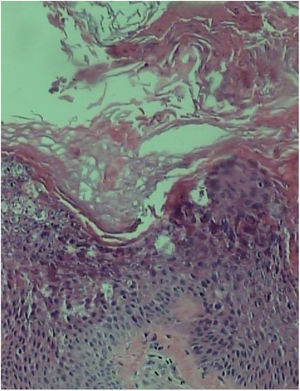

Skin biopsy in the extensor portion of the forearm showed acanthosis, papillomatosis, and hyperkeratosis with marked epidermolysis in the granular layer (Fig. 4).

In the histopathology, the hyperkeratotic lesions of the AEI revealed hyperkeratosis, acanthosis, and a thickened granular layer. Keratinocytes in the spinous layers and superior granulosa of the epidermis demonstrated cytoplasmic vacuolization and prominent keratohyaline granules.1,2,4,6 Basal keratinocytes appeared normal, but there was an increase in the number of mitoses. Regarding findings from electron microscopy, there were abnormal keratin filaments in the suprabasal keratinocytes, increase of kerato-hyaline granules in granule layer cells, and perinuclear accumulations of thickened tonofilament that formed an interrupted perinuclear ring.4,5